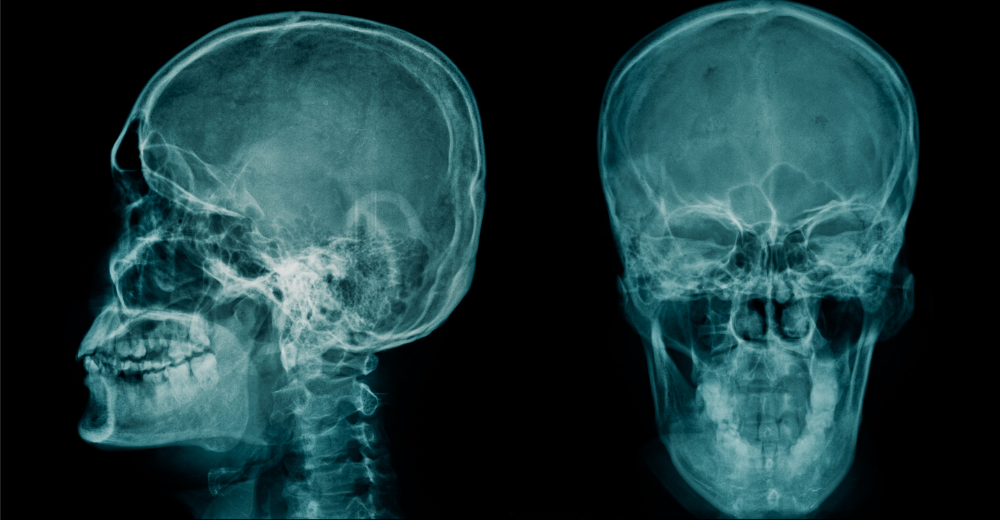

La Teleradiografia Cranio per Cefalometria è un esame radiologico non invasivo, fondamentale per l’analisi dettagliata della struttura cranio-facciale. Questo esame è spesso utilizzato nell’ortodonzia e nella chirurgia maxillo-facciale per valutare le relazioni tra le diverse componenti scheletriche del cranio e i denti. Al Poliambulatorio S-Medical Group di Sora, l’esame viene eseguito con tecnologie di ultima generazione e sotto la supervisione di professionisti esperti, garantendo massima precisione e affidabilità.

La Teleradiografia Cranio per Cefalometria è una metodica diagnostica che sfrutta le immagini radiografiche per ottenere una visione chiara e precisa delle strutture cranio-facciali. Questa tecnica è indispensabile per valutare la crescita e lo sviluppo del cranio e della mascella, fornendo dati essenziali per pianificare trattamenti ortodontici e chirurgici.

L’esame viene eseguito posizionando il paziente in piedi o seduto, con il capo stabilizzato per garantire una corretta acquisizione delle immagini. Durante l’esposizione, l’apparecchio radiologico cattura una visione panoramica del cranio e delle strutture circostanti, permettendo di misurare angoli, distanze e proporzioni che sono fondamentali per una diagnosi accurata.

Le immagini ottenute vengono successivamente elaborate con software avanzati, che aiutano a eseguire un’analisi cefalometrica dettagliata, evidenziando eventuali discrepanze scheletriche e dentali.

Grazie alla Teleradiografia Cranio per Cefalometria, è possibile ottenere una valutazione dettagliata di numerosi aspetti cranio-facciali, come:

• Posizione e inclinazione dei denti.

• Dimensioni e forma delle arcate dentali.

• Rapporti tra mascella e mandibola.

• Orientamento delle ossa cranio-facciali.

Queste informazioni sono cruciali per individuare problematiche come malocclusioni, disallineamenti dentali e anomalie scheletriche.